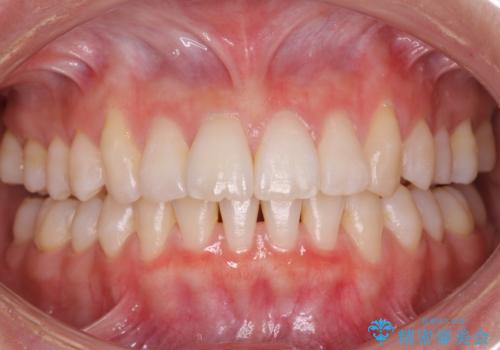

歯を抜かないで出っ歯を治したい

- 前歯が出ていることを主訴に来院。

歯を抜かずにマウスピース矯正をご希望でした。

歯と歯の間をわずかに削り、歯並びを少し横に拡大して並べました。

奥にすき間がなかったため後ろには下げていません。

沢山ひっこめるには4本抜歯でワイヤーの選択肢もありましたが、抜かないでできる範囲をご希望されました。

とがった形の歯列を整えるだけでもだいぶ印象は変わると思います。

今回歯列を広げた結果、上顎犬歯の歯肉は多少退縮しています。